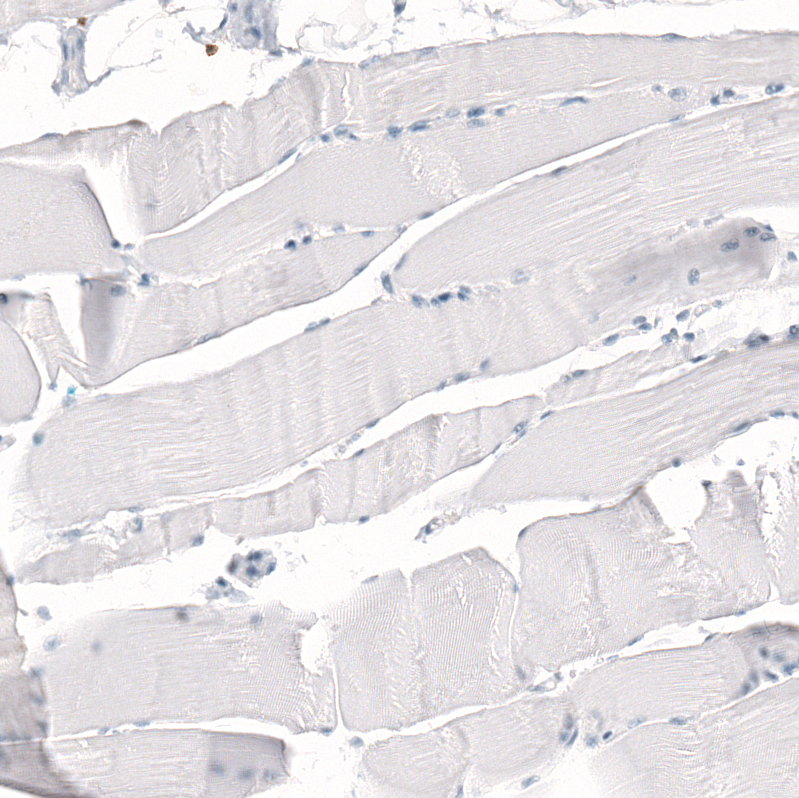

Immunohistochemistry analysis in human lymph node and skeletal muscle tissues using AMAb91783 antibody. Corresponding CD5 RNA-seq data are presented for the same tissues.